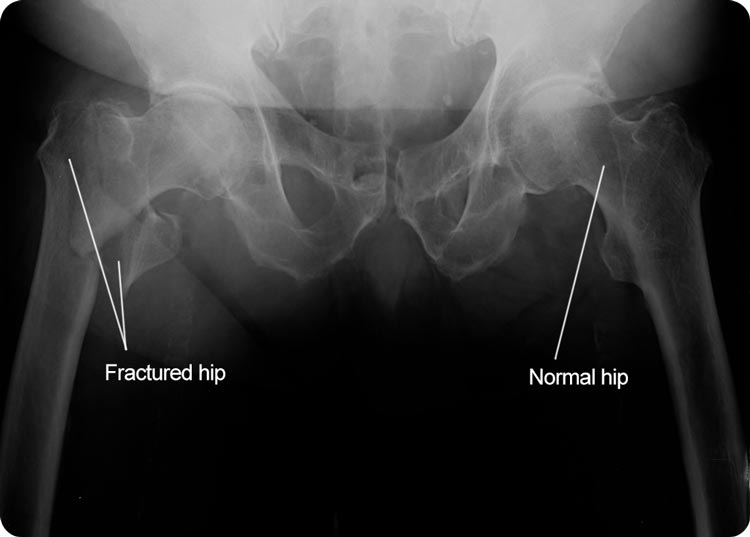

Medical Apparatus Imaging Guide fracture fixation